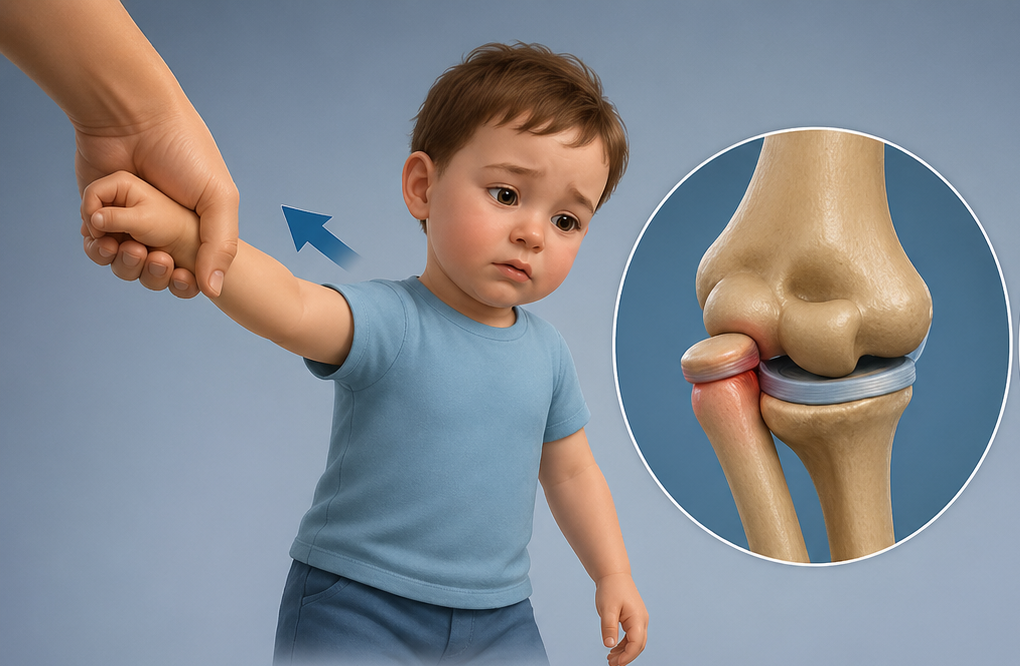

- Jo çdo dëmtim i meniskut duhet operuar.